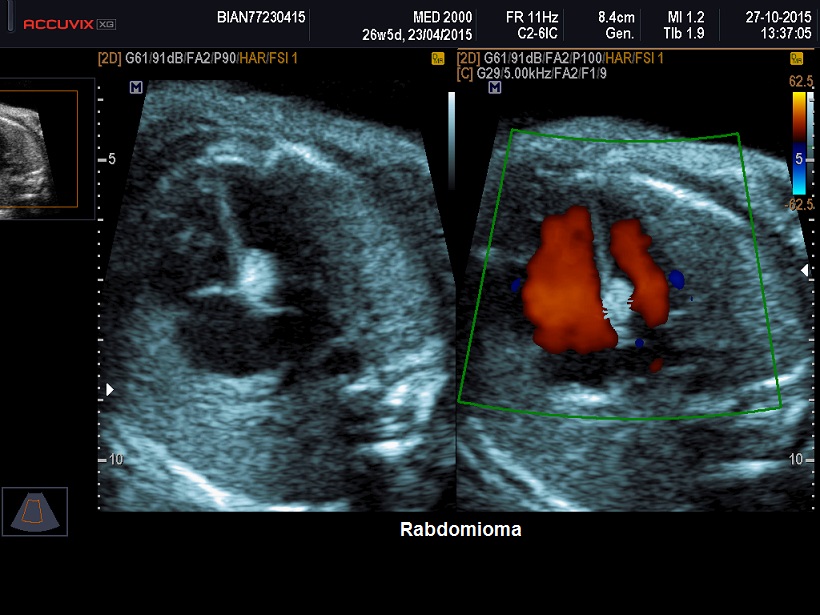

Rabdomioma: è la forma tumorale più

frequente rappresentando il 62% dei casi e nel 90% dei casi è multiplo. Si localizza nel contesto del setto interventricolare o può originare dalle pareti ventricolari. L'ecostruttura è iperecogena rispetto al miocardio e omogenea,

le dimensioni sono variabili. L'emodinamica cardiaca può essere modificata in

relazione al numero, alla localizzazione ed al volume dei tumori. Possono

determinare stenosi valvolare o aritmie che possono evolvere in idrope fetale. Può essere presente polidramnios.

calcificazioni e/o aree cistiche. Nel feto il riscontro di una massa intracardiaca orienta statisticamente verso la diagnosi di rabdomioma, specie se la lesione è multipla. Una caratteristica patognomonica, in caso di interessamento del setto ventricolare del rabdomioma, è il fatto che questo tipo di tumore coinvolge entrambi i lati del setto.